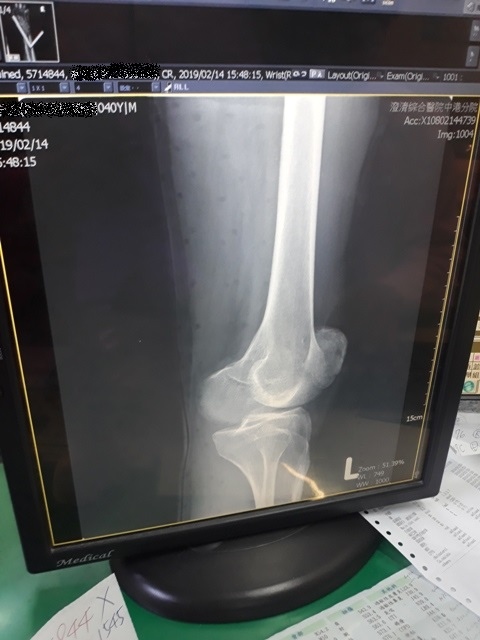

右手X光↓

進入門診前,我自認為手比腳恢復還快,因為比起一開始,手指比較能出力了,手腕可轉動的範圍也變大了。腳因一直用副木石膏固定住,不能動,所以也不知恢復多少。進入門診後,黃醫師說斷裂的骨頭都沒移位。手沒什麼進展(骨頭不會長那麼快),腳的部份下回再來復診時,可能會恢復的較快了。

手沒什麼進展這件事,讓我比較吃驚,詢問黃醫師,手如果也改用副木,會不會比較好,黃醫師說,他個人是認為沒什麼差。他看著X光片照出來的結果,說開刀或不開刀他覺得都差不多。